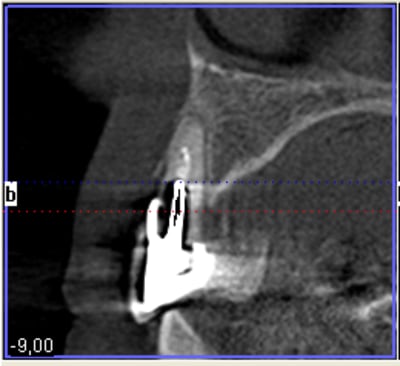

un petit exemple de ce matin: extraction des piliers 12 et 14, curetage, comblement avec du bio-oss de la dépression osseuse vestibulaire au niveau de l'inter 13, comblement des alvéoles 12 et 14 au genos et recouvrement par 2 pédicules conjonctifs. Temporisation avec un partiel amovible.

Niveau 12 slt3od - Eugenol

Niveau inter trai6z - Eugenol